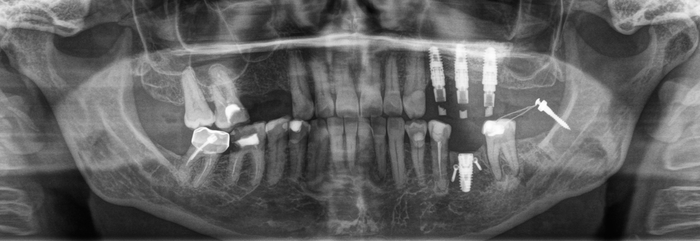

После операции необходимо подождать 4 месяца перед установкой формирователя десны.

(На данном снимке виден зазор между формирователем и имплантатом. Как раз поэтому полезно делать контрольные снимки. Формирователь я дотянул)

Зуб и имплантат на своих местах. Теперь никаких проблем с изготовлением коронки не будет: